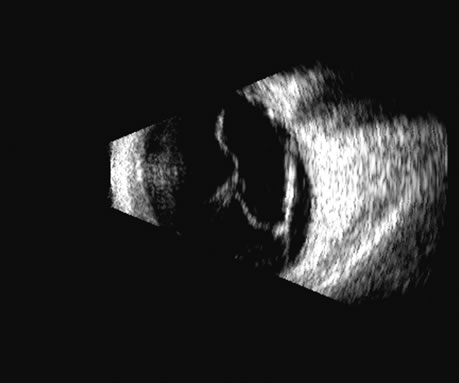

| The retina is a highly reflective surface (specular reflector) and

can be seen to always maintain its connection to the optic nerve, even

when drawn into an organized detachment. It may not be attached

at the ora serrata in giant tears, but otherwise it generally maintains

the two “landmark” attachments of optic nerve and ora serrata (Fig. 13), which can aid in differentiating the retina from the PLM of the

retracted vitreous and from the choroid, in which the detachment may

extend anterior to the ora and rarely extend back behind the vortex veins

to the nerve (Fig. 14).14 Two-dimensional scans through complex three-dimensional structures, such as preretinal membranes and proliferative membranes, can be confusing unless mapped with three-dimensional conceptualization techniques. Bronson and colleagues15 have emphasized three-dimensional thinking. Although new digital three-dimensional ultrasound systems allow direct volume visualization, it remains useful to understand the technique of conceptualizing three-dimensional structures from individual sections.16 Preretinal membranes (Fig. 15), which may resemble traction detachments in thickness and reflectivity, can often be identified by turning the scan plane of the B-scanner at right angles: the disciform retinal elevation is still seen while the linear nature of a traction sheet is revealed.17 A three-dimensional rendering of a retinal detachment can directly show the conformation of three-dimensional structures (Fig. 16), and images of individual planes can be perceived. Schisis can be difficult to differentiate from a peripheral detachment based on echo amplitude, but may be suspected based on location and other clinical factors, such as age and symptomatology. Schisis is usually convex and may have lower amplitude than a retinal echo. |